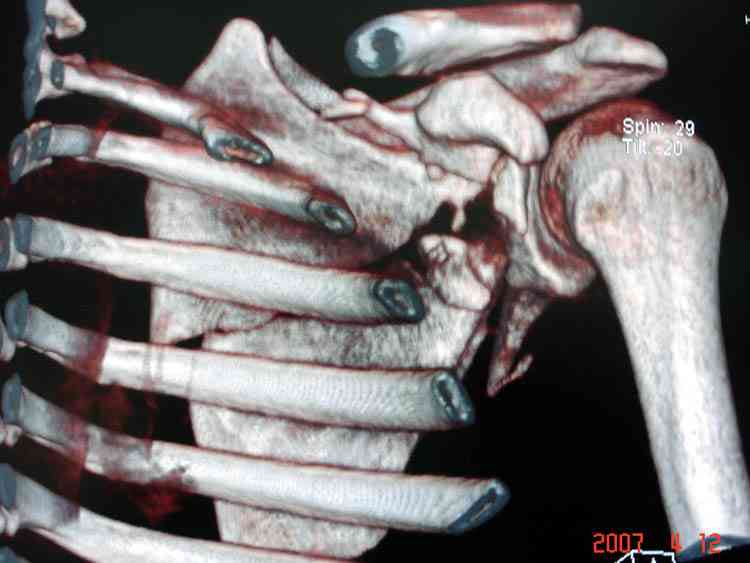

К-томографические и Трехмерные(3D)снимки крайне важны для определения внутрисуставных переломов и классификации.

На снимке (№6 компьютерная томограмма и 3D №7) перелом клювовидного отростка.

Передним дельтопекторальным Bankart доступом намного легче провести фиксация отростка, но тогда репозиция и фиксация колонн затрудняется, поэтому был применен стандартный Judet задний доступ.

Репозицию смогли сделать пальцами через щель между

шейкой и телом лопатки (последний 3D снимок)